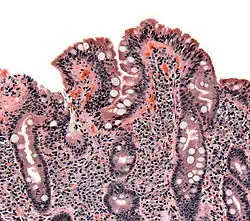

Whipple's disease: Alcian blue with apparently eosin counterstain enlarged villus with many macrophages